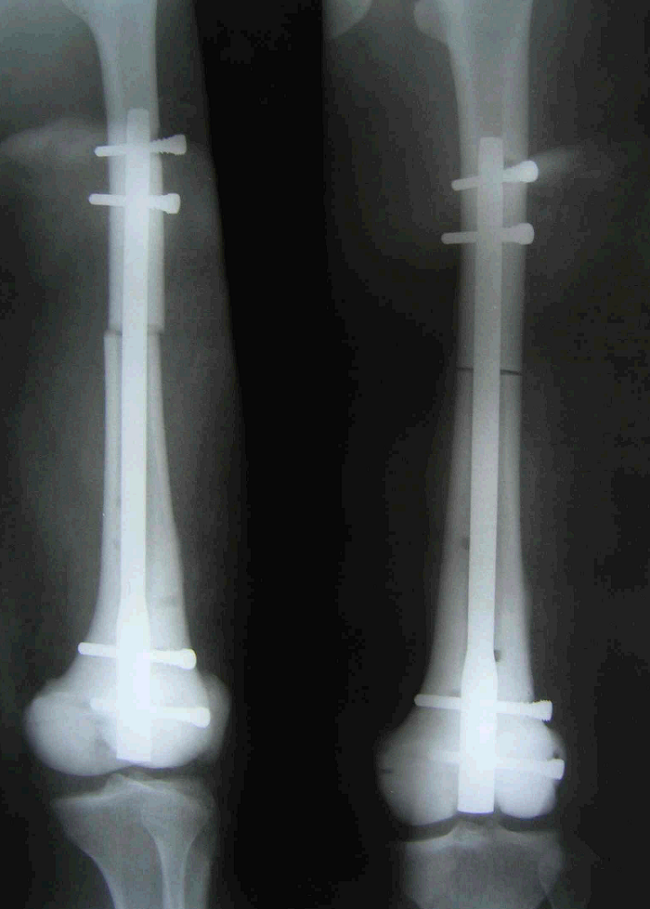

5、病例5:男 65岁 左胫骨上段毛细血管扩张性骨肉瘤,因活检术后持续性出血,行大腿中段截肢术

图 26术前X线片

a:正位 b:侧位

图 27 6周后病变范围显著扩大

图 28 术前CT横断面象

图 29 术前CT冠状面象